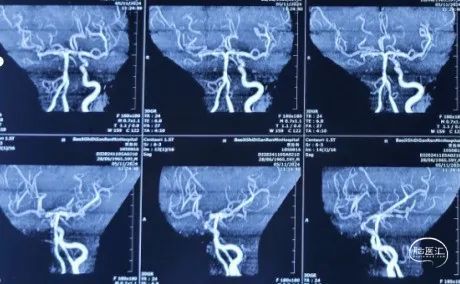

DSA造影(2024.11.07)

右侧颈内动脉起始段闭塞,动脉晚期可见颈动脉颅内段浅淡显影。

前交通动脉开放,右侧大脑中动脉显影良好。

右侧后交通动脉开放,右侧颈动脉颅内段浅淡显影。